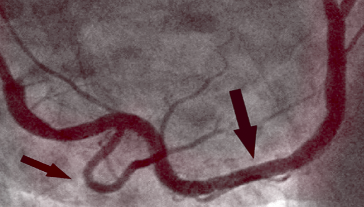

PRED KÚROU

Fotografia vľavo ukazuje stenózu pravej koronárnej artérie u 66-ročného muža, diagnostikovaná invazívnou koronárnou angiografiou. Existuje významná proximálna stenóza spôsobená kalcifikovaným plakom, ktorý blokuje prietok krvi.